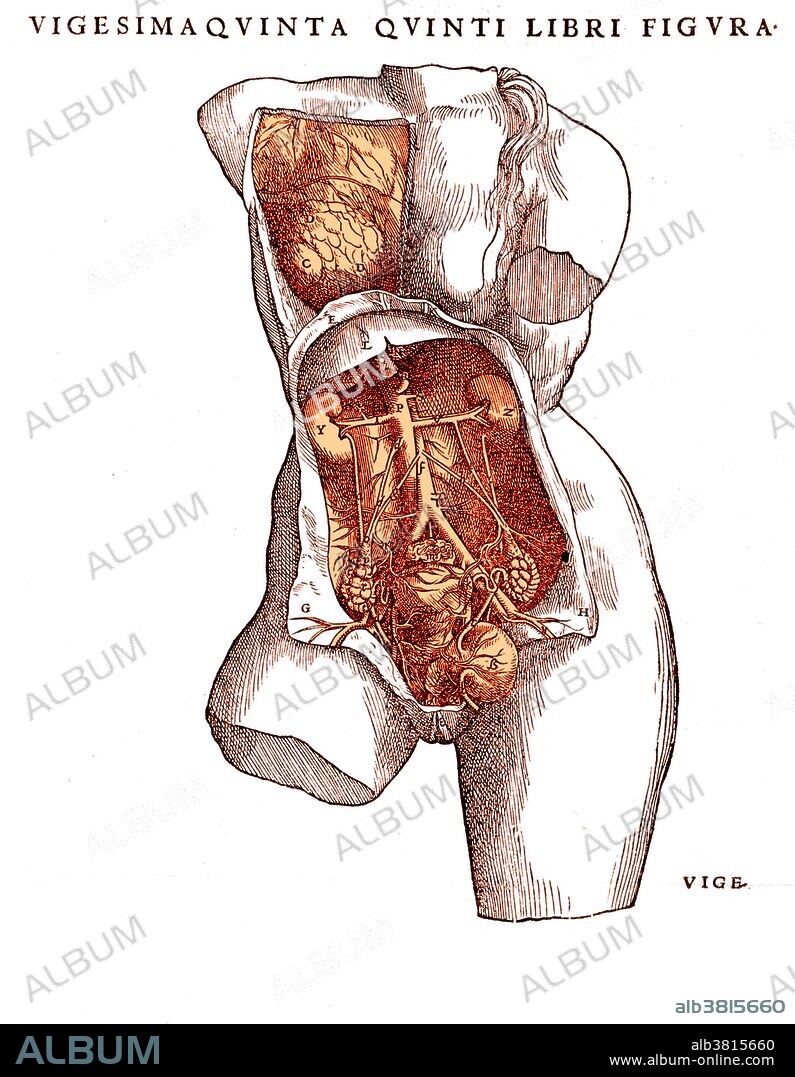

Female Reproductive Organs, Vesalius, 1543

Anatomical illustration showing female reproductive organs, from Andreas Vesalius's De humani corporis fabrica, 1543. Andreas Vesalius (1514-1564) was a Belgian anatomist who founded modern anatomy. He revolutionized the study of anatomy, ending the teaching of Galen and practicing direct observation by dissection. His results were published in 1543 in the famous book De Humani Corporis Fabrica (On Structure of the Human Body). The first accurate work on human anatomy, it included many descriptions and fine woodcuts. After this early success, he became a court physician and all but gave up research.